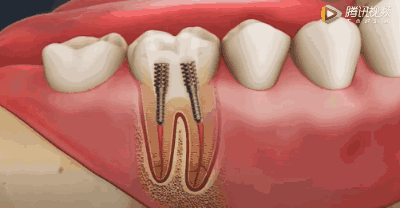

用根管钻扩大根管

方便进行下一步的植根工作。

植根、封牙、夯实

因牙体缺损过多,导致牙的强度(承受力量的性能)大幅度下降,不能很好地承受咀嚼力量。植根(打桩)的目的是增加牙根及牙冠的强度,增加患牙的稳固。